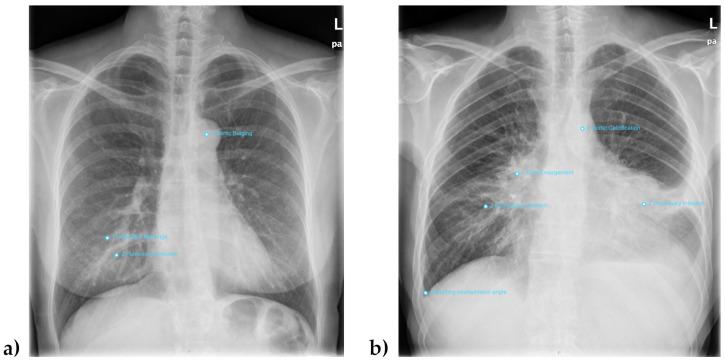

This retrospective study evaluated a commercial deep learning (DL) software for chest radiographs and explored its performance in different scenarios. A total of 477 patients (284 male, 193 female, mean age 61.4 (44.7-78.1) years) were included. For the reference standard, two radiologists performed independent readings on seven diseases, thus reporting 226 findings in 167 patients. An autonomous DL reading was performed separately and evaluated against the gold standard regarding accuracy, sensitivity and specificity using ROC analysis. The overall average AUC was 0.84 (95%-CI 0.76-0.92) with an optimized DL sensitivity of 85% and specificity of 75.4%. The best results were seen in pleural effusion with an AUC of 0.92 (0.885-0.955) and sensitivity and specificity of each 86.4%. The data also showed a significant influence of sex, age, and comorbidity on the level of agreement between gold standard and DL reading. About 40% of cases could be ruled out correctly when screening for only one specific disease with a sensitivity above 95% in the exploratory analysis. For the combined reading of all abnormalities at once, only marginal workload reduction could be achieved due to insufficient specificity. DL applications like this one bear the prospect of autonomous comprehensive reporting on chest radiographs but for now require human supervision. Radiologists need to consider possible bias in certain patient groups, e.g., elderly and women. By adjusting their threshold values, commercial DL applications could already be deployed for a variety of tasks, e.g., ruling out certain conditions in screening scenarios and offering high potential for workload reduction.

这项回顾性研究评估了一款用于胸部X光片的商用深度学习(DL)软件,并探讨了其在不同场景下的性能。共纳入477例患者(男性284例,女性193例,平均年龄61.4(44.7 - 78.1)岁)。作为参考标准,两名放射科医生对七种疾病进行独立解读,共报告了167例患者的226项检查结果。单独进行自动DL解读,并使用ROC分析对照金标准评估其准确性、敏感性和特异性。总体平均AUC为0.84(95%可信区间0.76 - 0.92),优化后的DL敏感性为85%,特异性为75.4%。在胸腔积液方面取得了最佳结果,AUC为0.92(0.885 - 0.955),敏感性和特异性均为86.4%。数据还显示,性别、年龄和合并症对金标准与DL解读之间的一致性水平有显著影响。在探索性分析中,当仅筛查一种特定疾病且敏感性高于95%时,约40%的病例可以正确排除。对于一次性综合解读所有异常情况,由于特异性不足,只能实现边际工作量的减少。像这样的DL应用有望实现胸部X光片的自动综合报告,但目前仍需要人工监督。放射科医生需要考虑某些患者群体(如老年人和女性)可能存在的偏差。通过调整阈值,商用DL应用已经可以用于各种任务,例如在筛查场景中排除某些情况,并具有很大的工作量减少潜力。